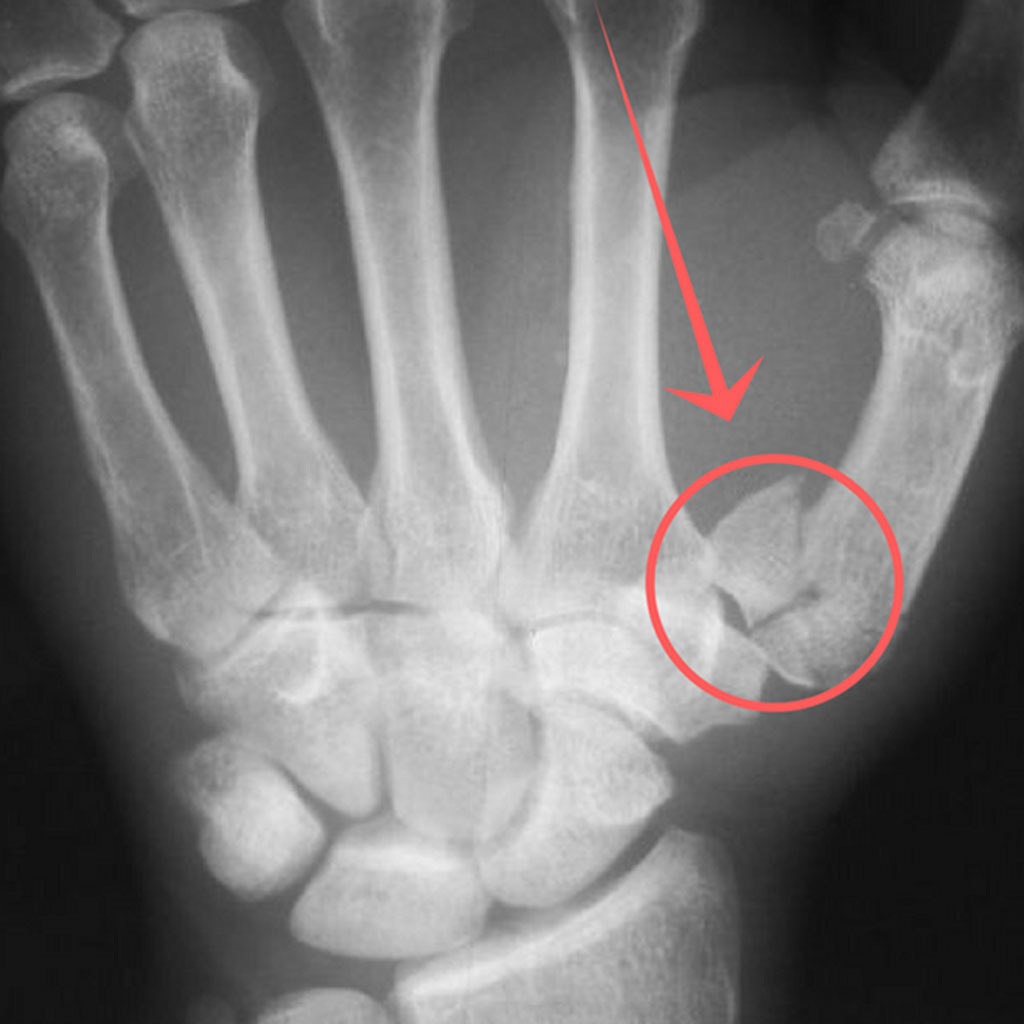

반대로 깁스 또는 보다 강한 고정이 필요한 경우는 다음과 같습니다.

- 골절로 인해 뼈가 어긋난 경우

- 관절면이 손상된 경우

- 여러 조각으로 부러진 분쇄 골절

- 스플린트 착용 후에도 통증과 불안정성이 지속되는 경우